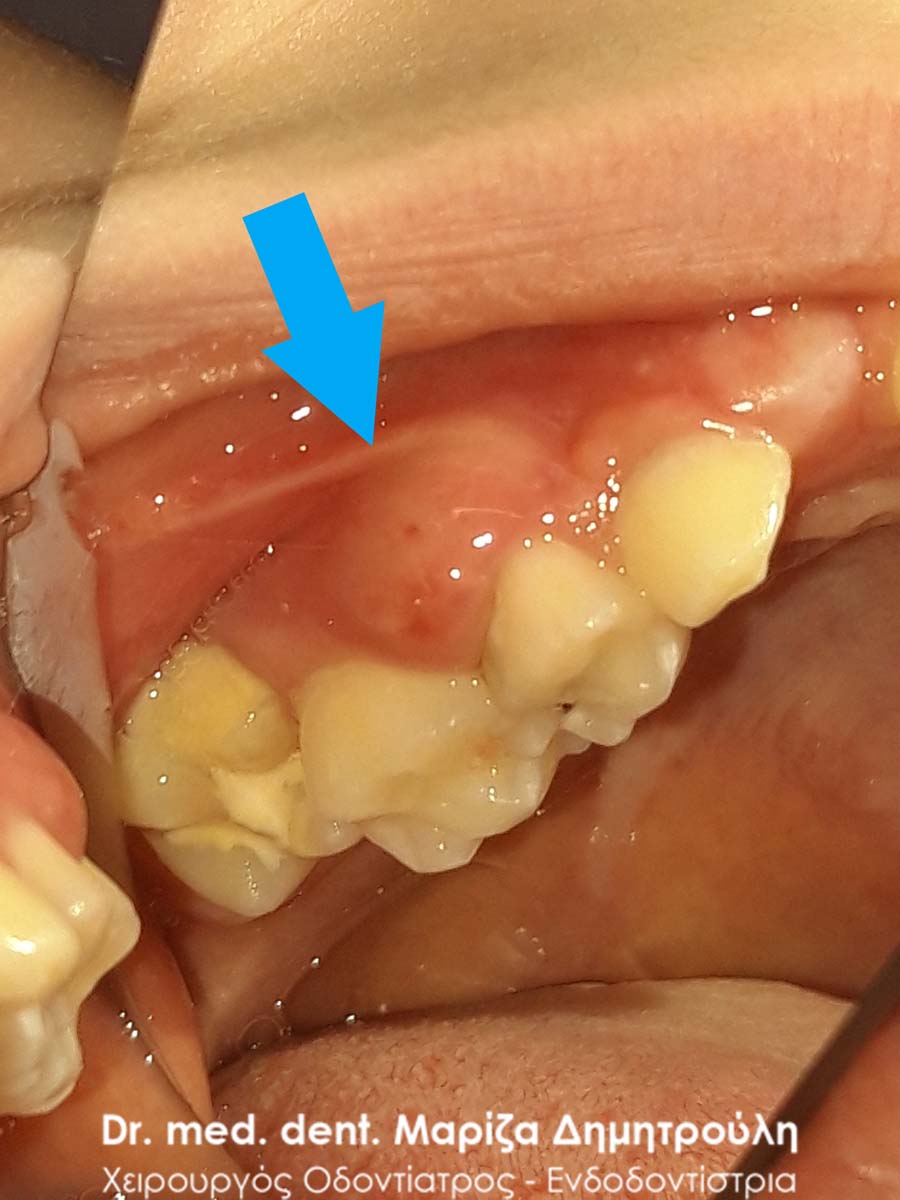

Pus / Eiter in primary tooth